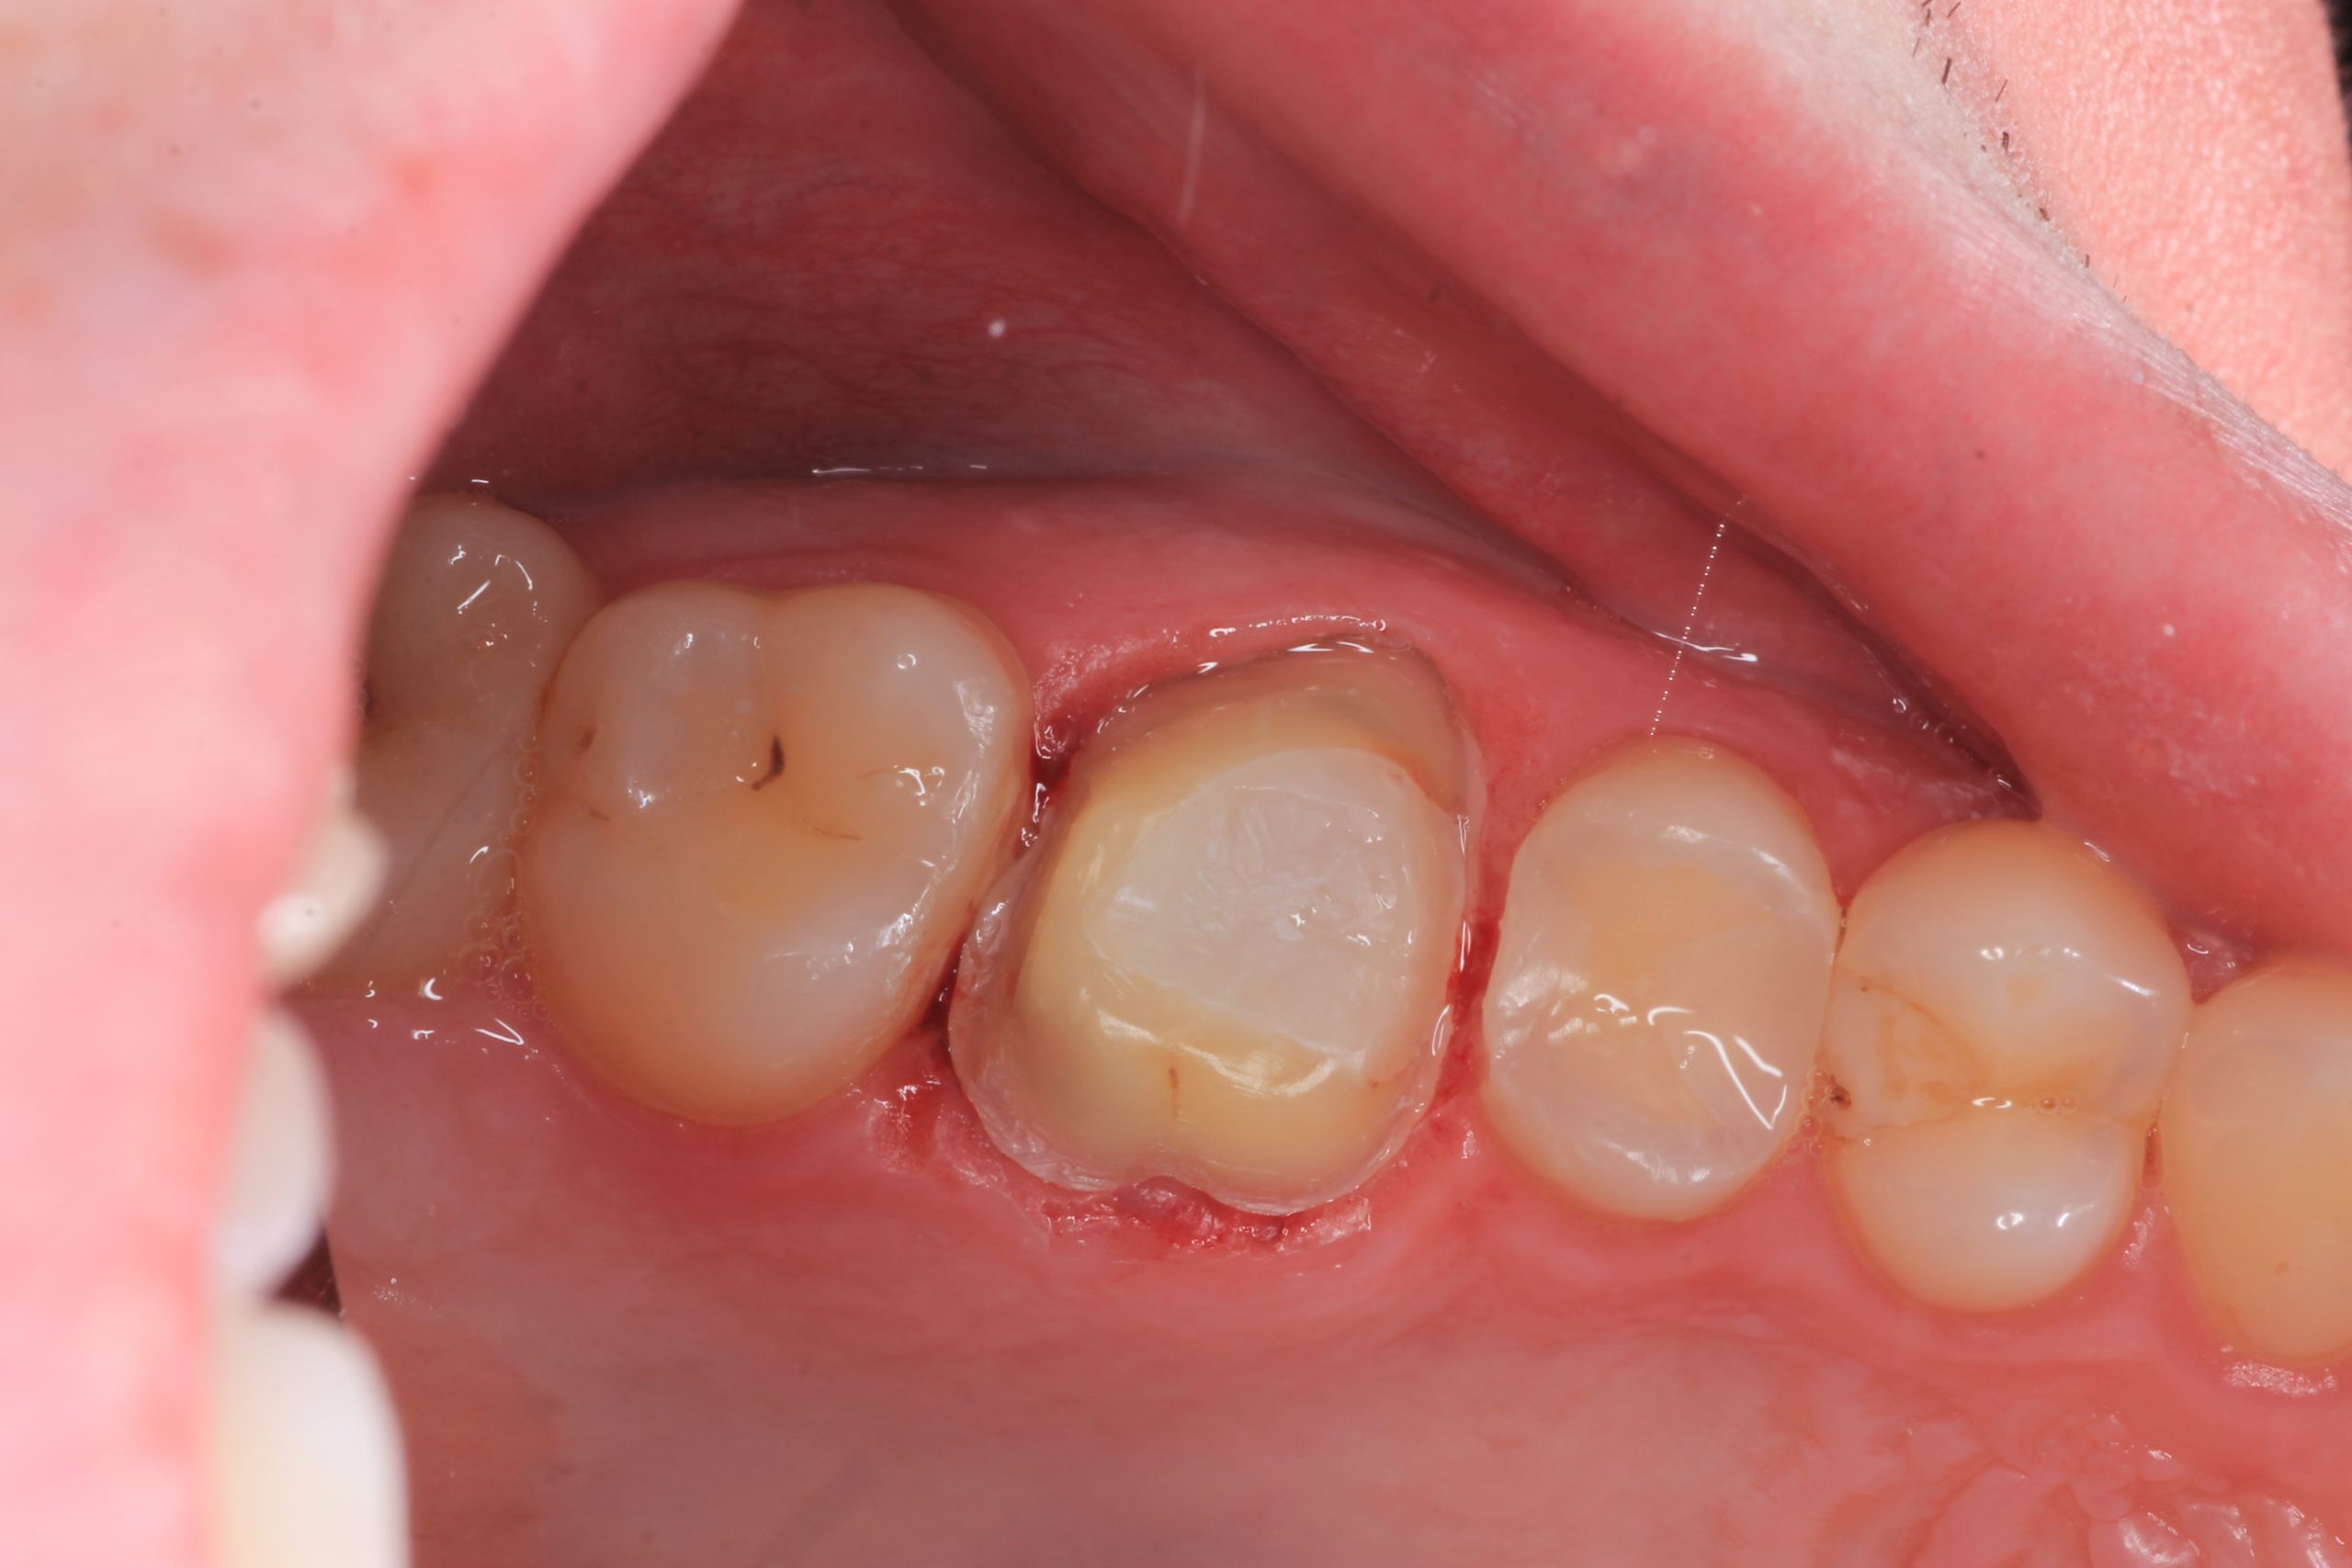

Once numb, most patients feel only light vibration and pressure. Even severe toothache typically eases immediately after anaesthesia takes effect. - Microscope-guided access

Under bright magnified light, a tiny opening is created and every canal located — even the hidden ones that often cause failures elsewhere. - Cleaning and shaping

The canals are shaped with flexible rotary files to create an ideal form for irrigation while preserving tooth strength. - Disinfection